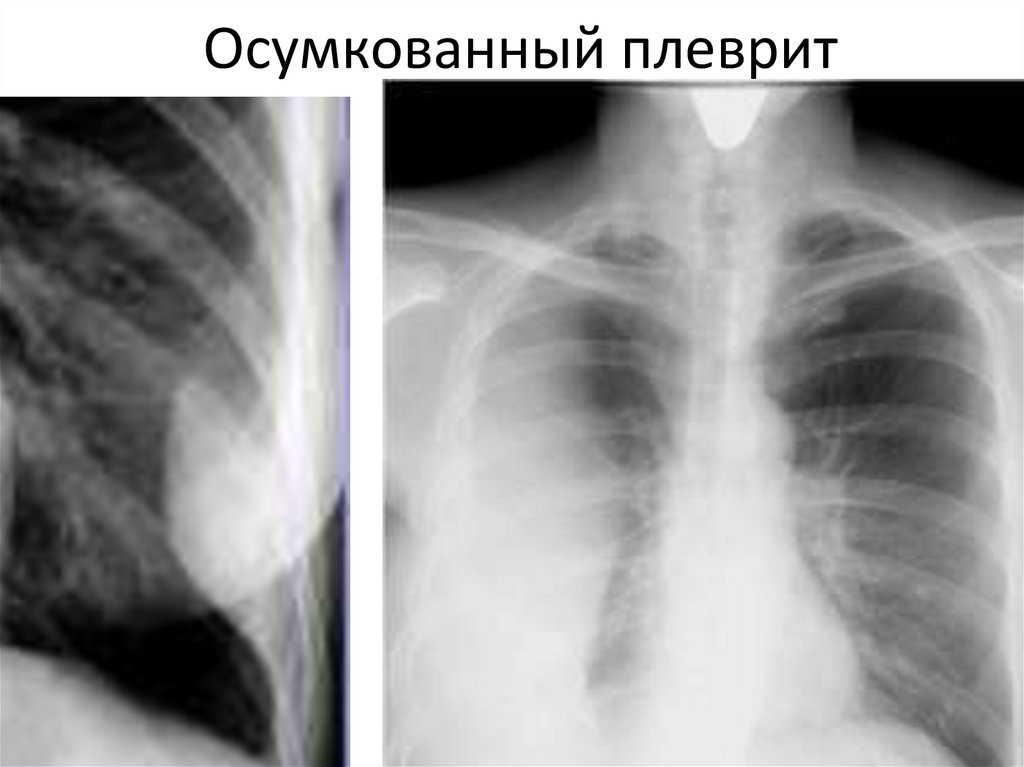

Осумкованный плеврит